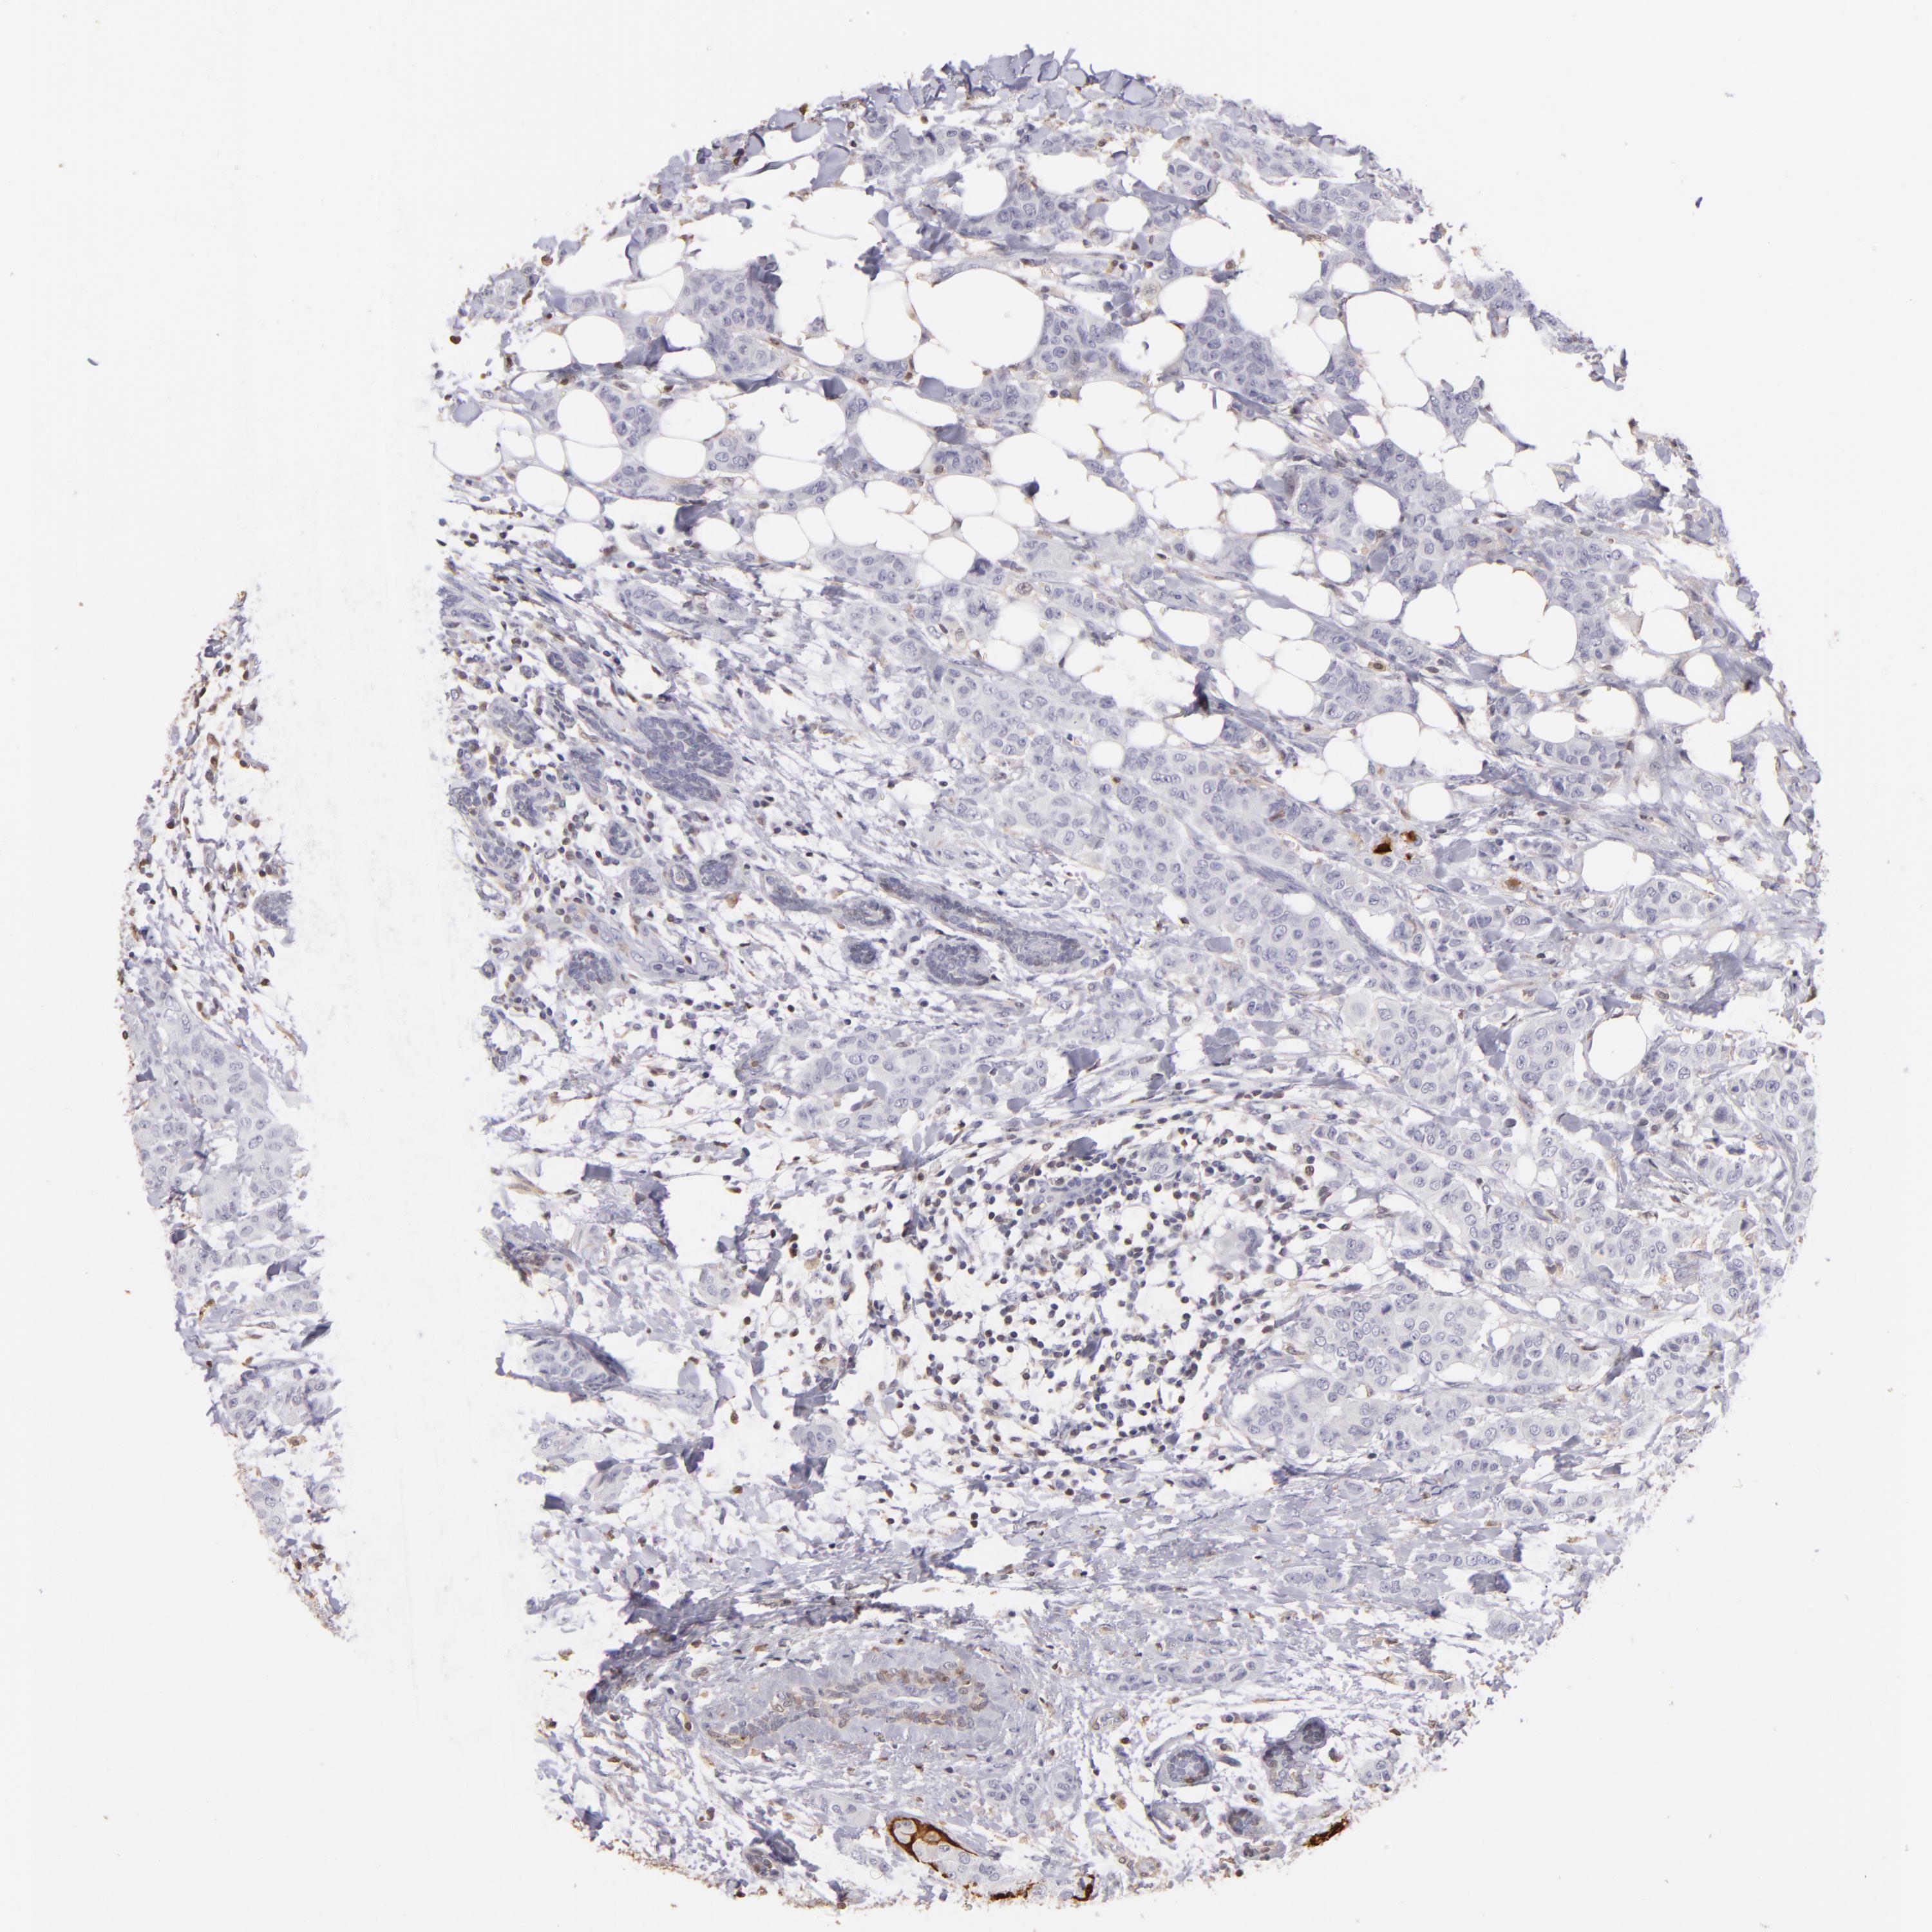

CANCER BREAST CANCER Show tissue menu

BRCA TCGA BRCA VALIDATION PROTEIN EXPRESSION

ANTIBODIES

AND

VALIDATION